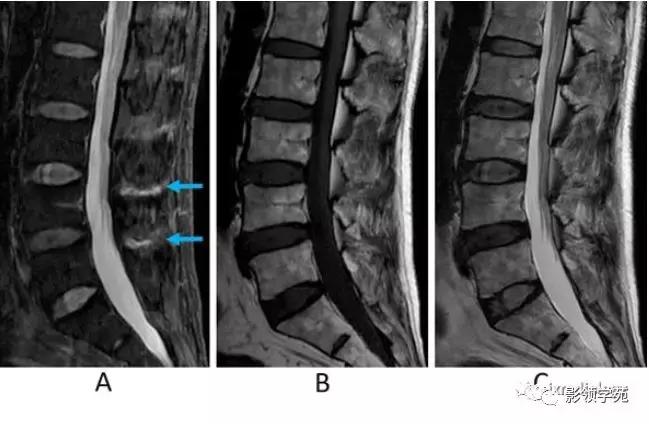

图11:棘间韧带炎。男,70岁;腰痛。

A:STIR矢状面图像,B:T1WI矢状面图像,C:T2WI矢状面图像。

在STIR序列上可见棘突之间L4 /5和L5/S1(A箭)水平的高信号。 这些软组织异常信号很难在T1WI或T2WI序列上显示(B,C)。